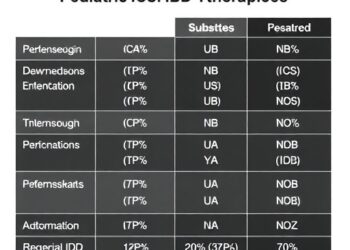

Cutaneous Risks in Advanced Pediatric IBD Therapies

In a groundbreaking study published in Pediatric Research, researchers have shed new light on the risk factors associated with cutaneous...